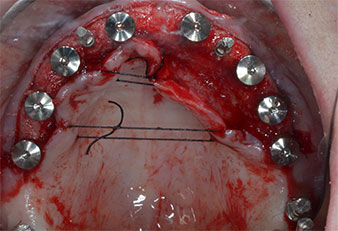

Drei Jahre später war es Zeit für eine gleichartige Oberkieferprothese. Basierend auf der DVT-Planung wurde durch Verwendung kurzer Implantate eine Sinusaugmentation vermieden und die geplanten Implantatpositionen wurden mit einer Bohrschablone auf den Kieferkamm übertragen (Abb. 1 und 2).

Ein flammenförmiges, diamantiertes piezochirurgisches Instrument (Piezomed I1) wurde verwendet, um die Implantatpositionen zu markieren und die Pilotpräparationen durchzuführen (Abb. 3). Dabei wurde darauf geachtet, eine Auf- und Abbewegung mit reduzierter Leistung, voller Spülung und niedrigem Druck (unter 300 g) anzuwenden. Als Nächstes wurde ein Pilotinstrument (Piezomed I2A/I2P) zur initialen Erweiterung der Implantatlager auf einen Durchmesser von 2 mm verwendet (Abb. 4), gefolgt von einem 3-mm-Instrument (Abb. 5).

Wegen des relativ harten Knochens (D2) an den Positionen 11 und 21 wurden die 10 mm langen Implantatlager in diesem Bereich abschließend mit einem 4-mm-Spiralbohrer, dem chirurgischen Winkelstück WS-75 L von W&H und dem W&H Implantmed Implantologiemotor in Verbindung mit dem optionalen W&H Osstell ISQ module präpariert. Im Gegensatz dazu wurde der weiche Knochen der Implantatlager im Seitenzahnbereich mit dem Piezomed I3P auf den abschließenden Durchmesser von 3 mm erweitert. Die Implantate wurden dann transgingival eingesetzt, die Einheildauer betrug drei Monate (Abb. 6-10). Die vorhandene Prothese wurde auf vier provisorischen Implantaten abgestützt (Abb. 8).